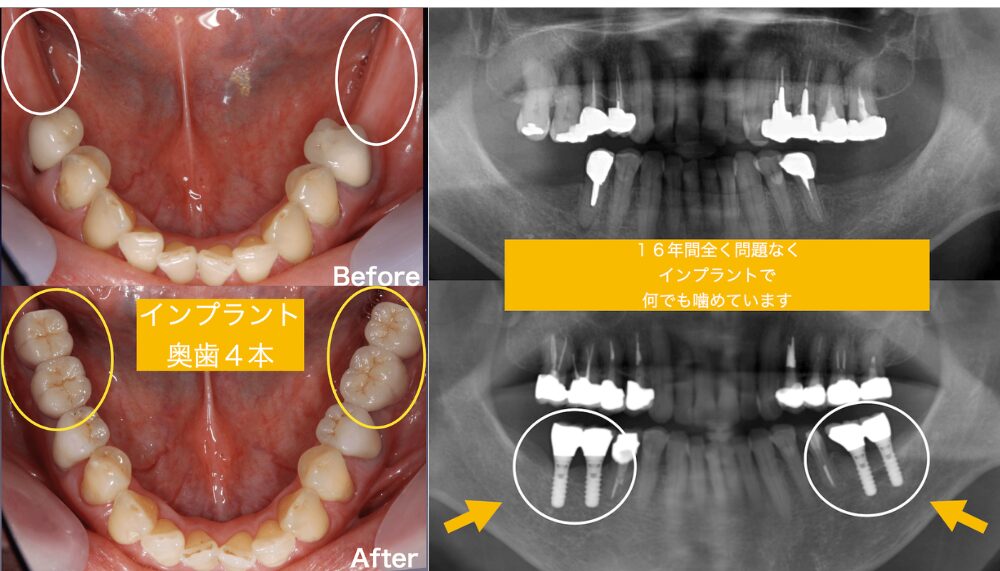

インプラント16年間経過症例でも全く問題なく経過良好

こちらの患者様は、下顎の奥歯4本に対して16年前にインプラント治療を行っており、それらのインプラントは現在もなお、まったく問題なく良好に機能しています。

しかし今回、インプラントとは別の部位である「ご自身の歯」にトラブルが生じました。割れてしまったその歯は、約40年前に他院で治療された歯であり、私が16年前に再治療を行った際にも「残存歯質が少なく、将来的に問題が起こる可能性が高い歯です」と患者様にお伝えしていた部位でした。

16年間にわたり、半年に一度の定期メンテナンスを継続し、噛み合わせも綿密にチェックしてきましたが、ついにその歯に亀裂が入り、破折という結果に至りました。すぐに抜歯即時インプラントで4ヶ月かからずに全ての治療が終了しまたメンテナンスに戻って頂きました。

裏を返せば、患者様はこの16年間、新たな大きな治療を行うことなく、良好な口腔環境を維持できていたということになります。これは、インプラントがしっかりと噛む力を分散し、他の歯への負担を軽減し続けてくれていた証とも言えるでしょう。

インプラントは「失った歯を補う治療」であると同時に、「残された歯を守る存在」でもある。この症例は、その事実を如実に物語っています。

>>16年ぶりの再治療。破折した左下奥歯を抜歯即時インプラントで再建した症例